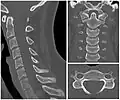

- X-ray of cervical vertebrae

- X-ray of cervical spine in flexion and extension